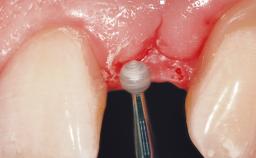

A 29-year-old female patient presented for treatment to replace the upper left central incisor tooth with an implant- supported restoration. The tooth had been intermittently symptomatic for the previous 12 months. The tooth had originally suffered trauma about 15 years previously. Several endodontic treatments had been performed, including an apicectomy procedure to retain the tooth. The patient was healthy and a non-smoker. She had reasonable expectations in regard to esthetic outcomes and the risk of marginal tissue recession following treatment. At medium smile, the gingival margins of the upper teeth were visible, with a display of 3 to 4 mm of the gingival margins. Gingival recession of tooth 21 and a discrepancy in the gingival levels between teeth 11 and 21 was observable during normal speech and smile.

Soft Tissue Anatomy Intact Defective

Soft Tissue Contour and Volume Slightly compromised